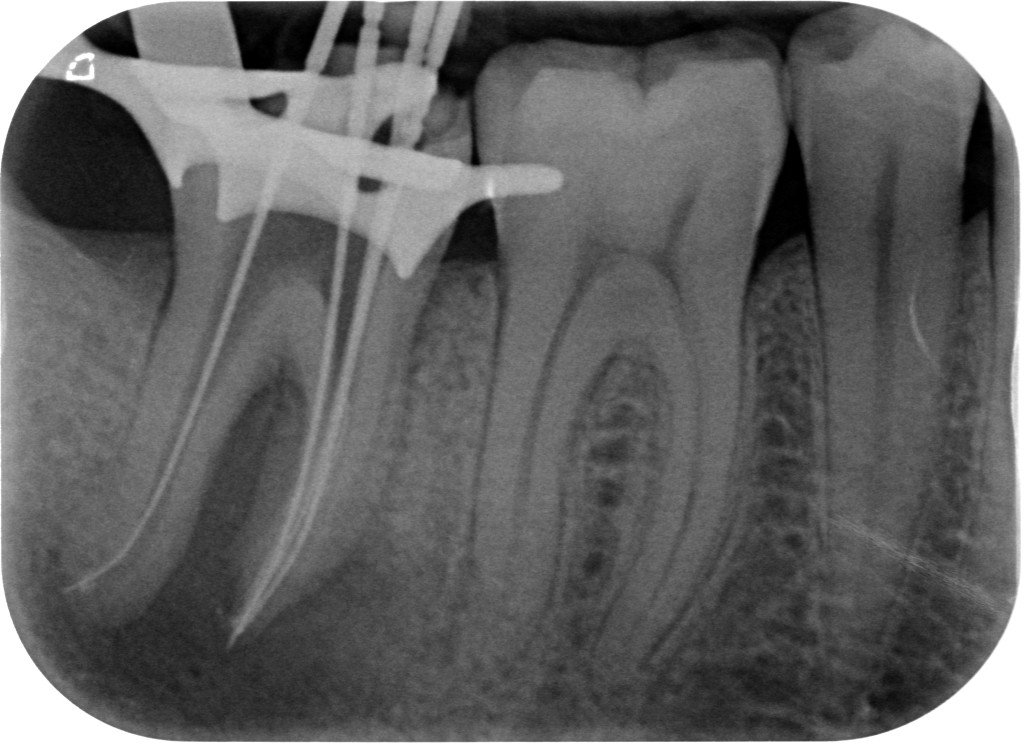

E come facevano? Si approfondivano di 2 mm nell’istmo tra i canali mesio-vestibolare e mesio-linguale con un fresina diamantata larga 1 mm in punta. Così facendo aumentavano il reperimento complessivo da 6 casi (tutti primi molari) a 42, di cui 21 secondi molari!

Il giorno dopo sul primo sesto inferiore che mi è capitato a tiro ho subito provato a inserire un Mtwo nell’istmo tra i canali MV e ML e….TADAAAAAAAN! Lo strumento si è subito impegnato!!!!

Di solito, essendo l’Mtwo viola uno strumento fenomenale per reperire e sondare in un sol colpo i canali stretti o calcificati, dopo aver sagomato i canali MV e ML provo a inserire questo strumento più volte nell’istmo tra i due canali suddetti. Se non sento un impegno allora mi approfondisco di 2 mm tra i canali MV e ML con una StartX 3 o , più spesso, con una fresina diamantata larga 0,8 in punta e il gioco è fatto.

Ora ti mostro qua sotto come reperire il canale mesiale-mediano.